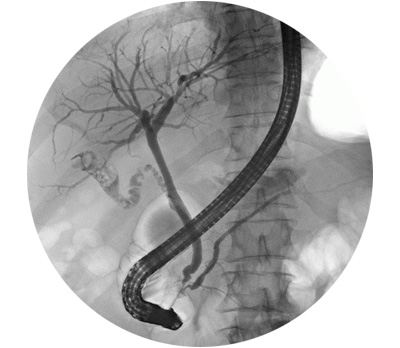

Safra yolu darlığı

Safra kanalı striktürü olarak da adlandırılan safra yolu darlıkları durumunda, safra kanalı daha küçük veya daha dar hale gelir. Safra kanalı karaciğerinden ince bağırsağa safra götüren kanaldır. Safra kanalının daralması durumunda safranın ince bağırsaklara akamaması nedeniyle yiyeceklerin sindirilmesini zorlaştırır. Safra, yağların sindirilmesinde yardımcı olan bir maddedir. Hafif safra darlığı olan hastalar herhangi bir semptom göstermeyebilir. Sarılık (cildin sararması), kaşıntı, açık renkte dışkılama ortaya çıkabilir.

Tanı

Öykü: Hastanın safra kesesi ameliyatı öyküsünün olması biliyer darlığın nedenin geçirilen cerrahiye bağlı olduğunu düşündürür. Ameliyat bölgesine yerleştirilen drenden safra gelmesi safra yolları ile ilgili problemin olduğu gösterir. Kilo kaybı ve sarılık varsa daha çok kanser ilişkili darlık vardır.

Kan analizi: Kanda safranın içinde bulunan bazı maddelerin yüksek olması safra yollarında daralmayı işaret edebilir.

Abdominal US: Safra yollarında problemleri göstermede ilk kullanılan Abdominal US: Safra yollarında problemleri göstermede ilk kullanılan radyolojik yöntemdir.

Magnetik Görüntüleme Kolanjiyopankreatikografi (MRCP): Safra yolları darlıklarının ayrıntılı incelemesi açısından önemli bir tanı aracıdır.

Tedavi

Safra yolu yaralanmalarının tedavisi girişimsel radyoloji, girişimsel gastroenetreroloji ve cerrahi bölümlerinin işbirliği ile birlikte yapılır. Darlığın yeri, nedeni ve derecesine göre stentleme ve cerrahi işlemler tercih edilir. Her bir hasta için özel karar vermek gerekir.